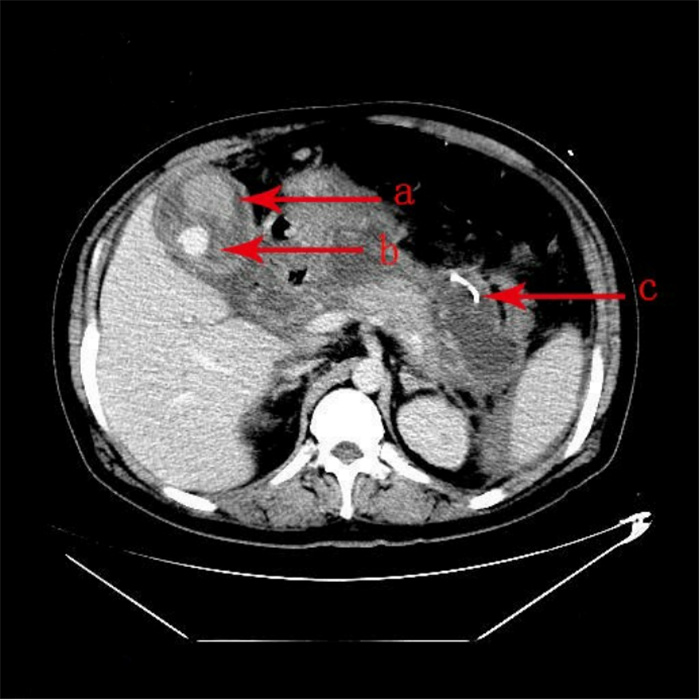

入院第57天,患者再次出现暗红色血便,伴阵发性右上腹痛,无发热、呕血,症状与之前相同。鉴于患者有活动性出血,再次复查胃镜:慢性浅表性胃炎伴糜烂。复查肝功能:γ-GT 844 U/L,TBil 43.6 μmol/L,NCBil 16.6 μmol/L,CBil 27 μmol/L,肝功指标再次回升,γ-GT、CBil明显升高,提示可能出现胆道梗阻。肝胆脾胰腺彩超复查:胆囊肿大、胆囊陈旧性稠厚淤胆(较前无明显变化),胰腺稍大并不均质改变。复查上腹CT:AP复查情况与之前相同,可能有胆囊出血(见图 2)。联合介入放射科行血管造影检查,常规局部麻醉下采用Seldinger技术由右侧股动脉入路,造影发现胆囊动脉分支出血(图 3),超选择胆囊动脉分支用明胶海绵颗粒行栓塞止血(图 4)。同时,行经皮经肝胆囊穿刺置管引流(图 5),病情稳定后带管出院,3月后予以拔除,择期行胆囊切除。

| 栓后造影胆囊动脉主干以远闭塞,造影剂外溢征象消失 图 4 胆囊动脉介入栓塞术后复查造影 |

| 置管置入内端位于胆囊中,位置良好 图 5 经皮经肝胆囊穿刺置管后腹部CT |

Thillai等[11]报道胆囊动脉出血给予栓塞治疗后会出现胆囊坏疽、继发腹腔感染的情况,本例患者行胆囊动脉栓塞后同时给予胆囊穿刺置管引流及冲洗治疗,未出现其报道的继发感染情况,后择期行胆囊切除术。